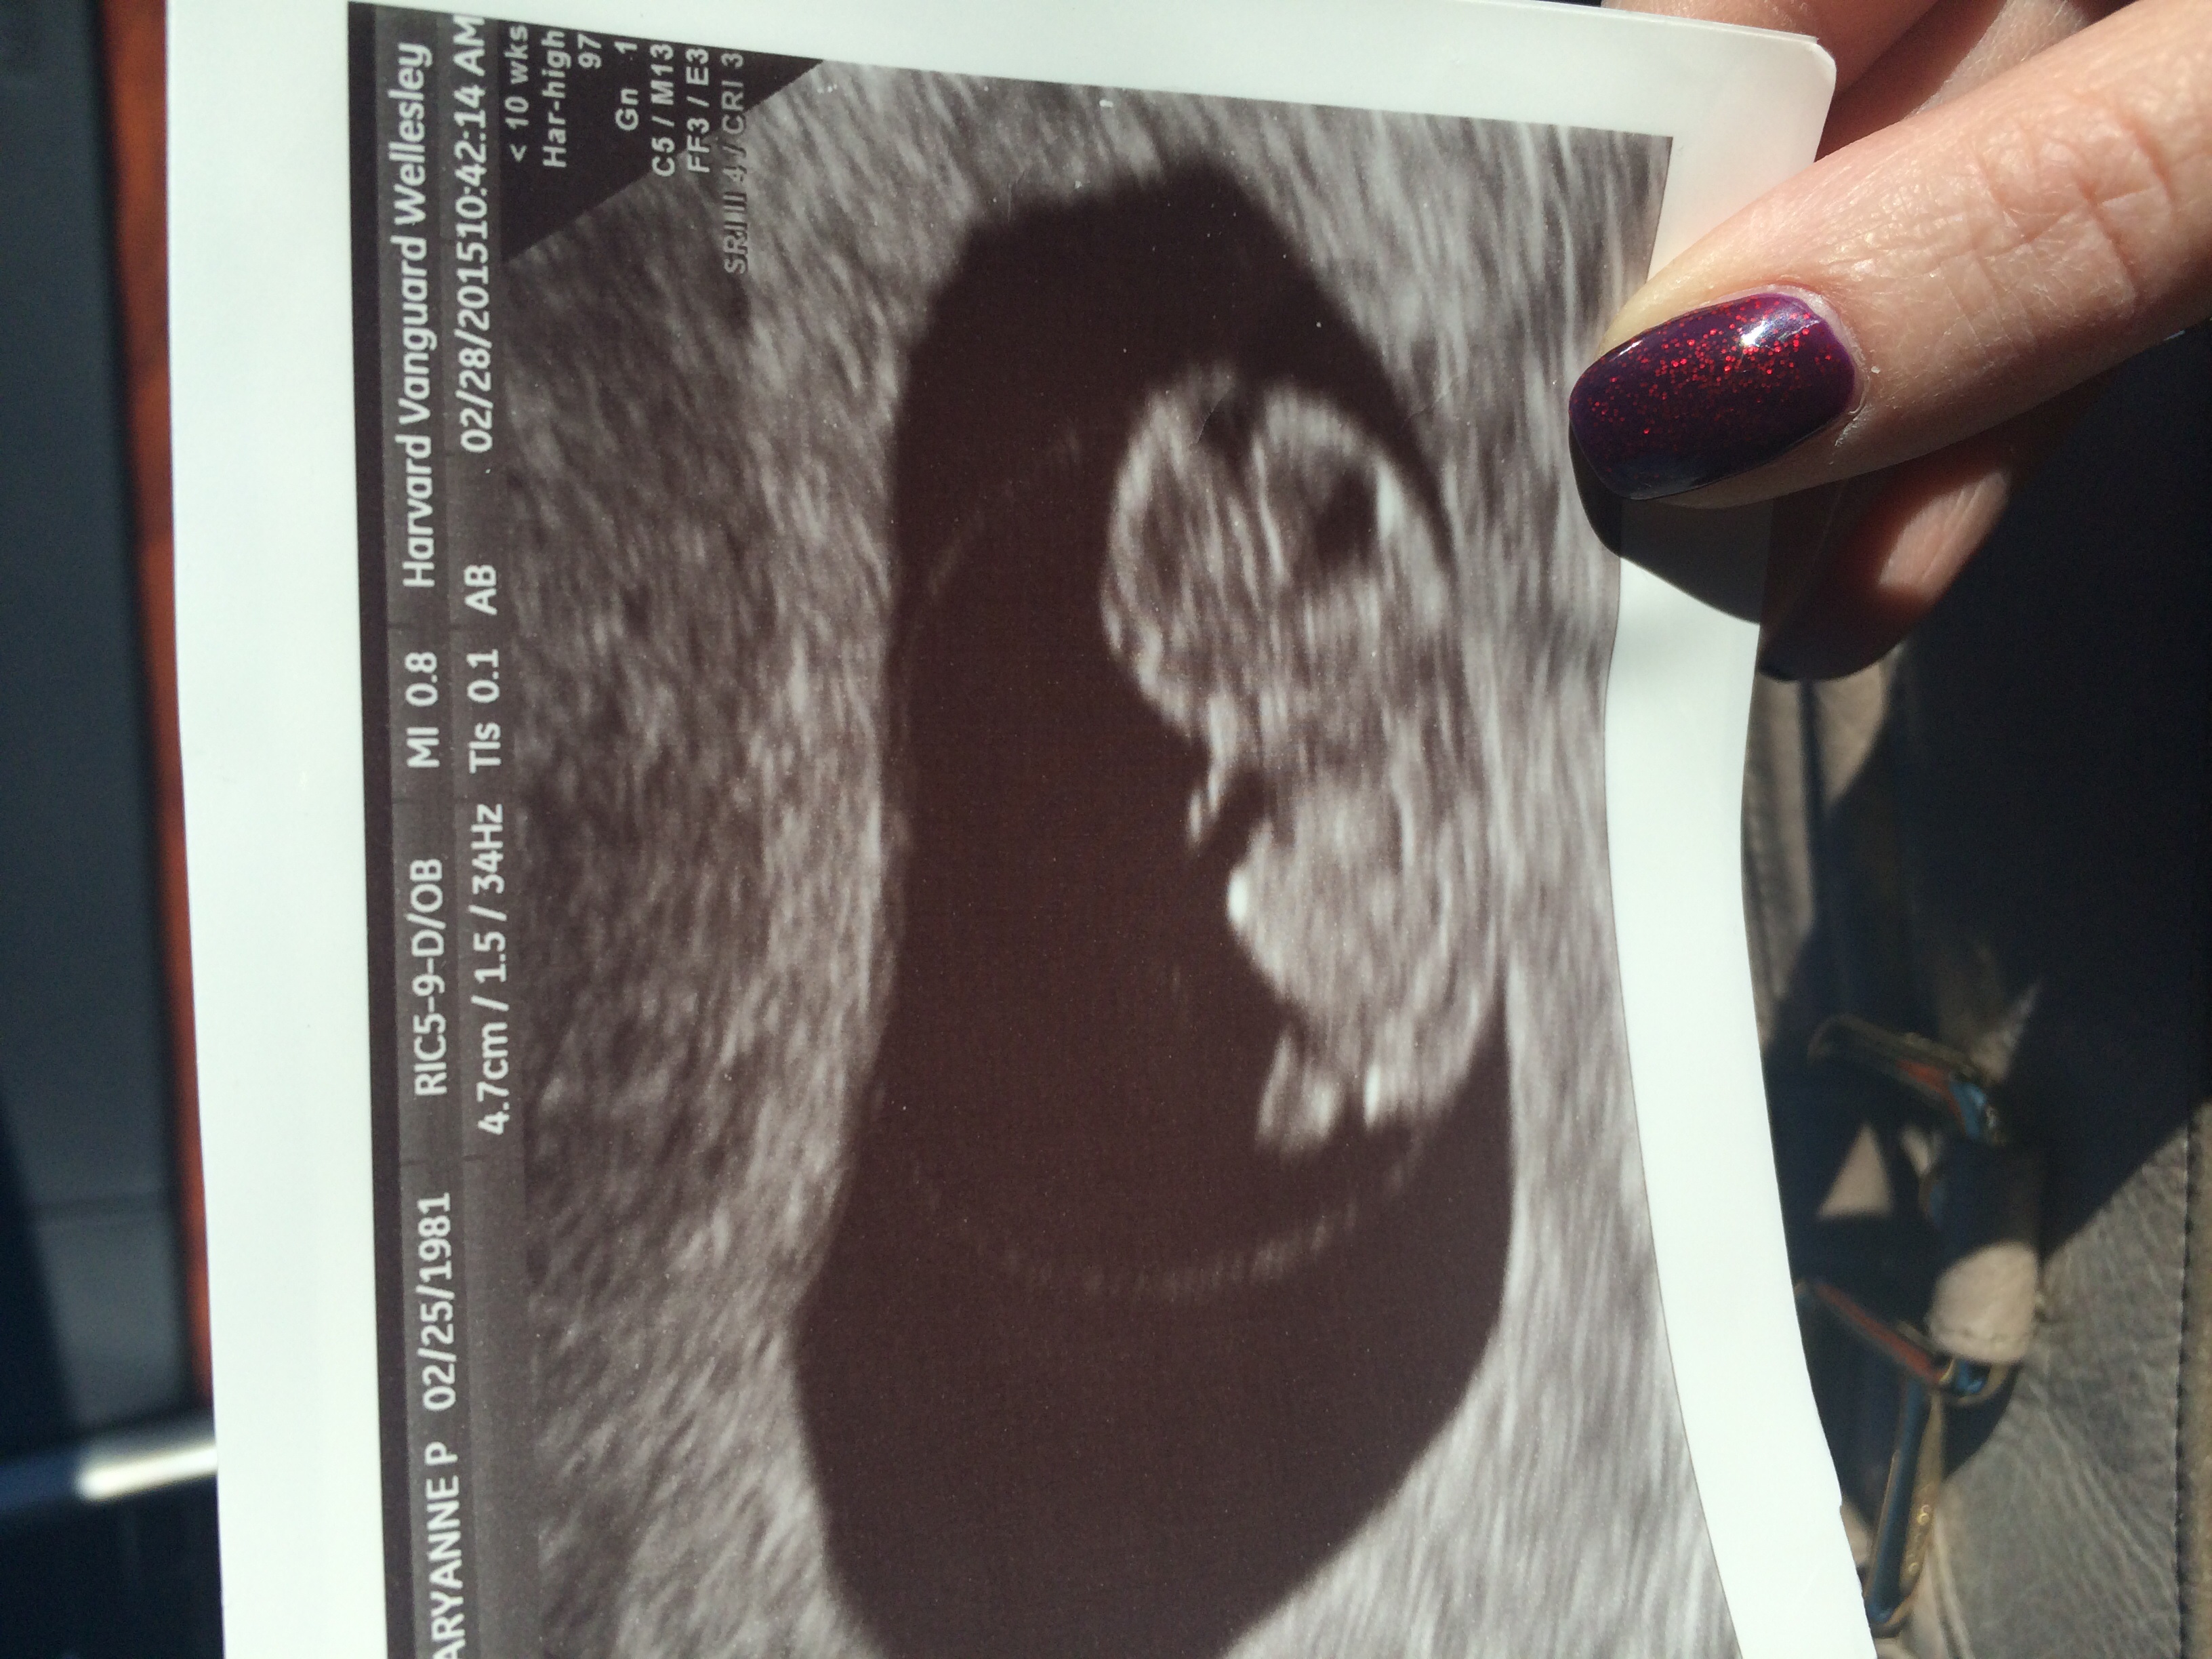

• I had my first ultrasound this morning! Our little bean has an extremely healthy heartbeat, and we're right on track to be due on October 25! My husband and I couldn't be any more excited. The look on my husband's face when he saw our baby on the screen was absolutely priceless!